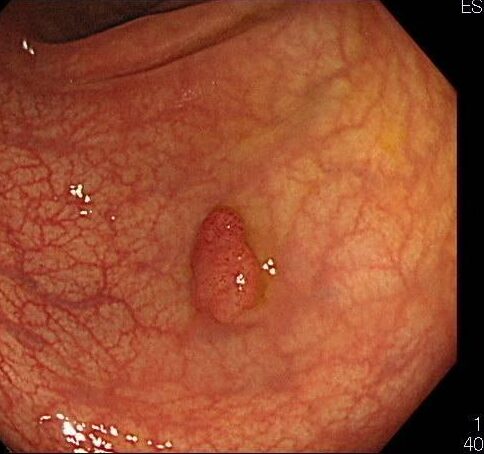

大腸ポリープ

大腸の粘膜にできる「いぼ」のことです。良性のできものですが、「がんになりやすいポリープ」「がんになりにくいポリープ」「がんにならないポリープ」の3つのタイプに分類されます。大腸がんのほとんどは、大腸ポリープが大きく成長したものです。自覚症状はなく、静かに大腸がんへと成長していきます。